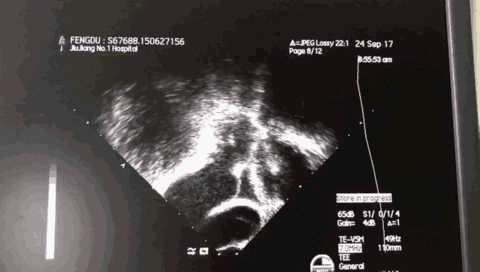

术前超声:

TEE 45:

TEE 90:

TEE 135: